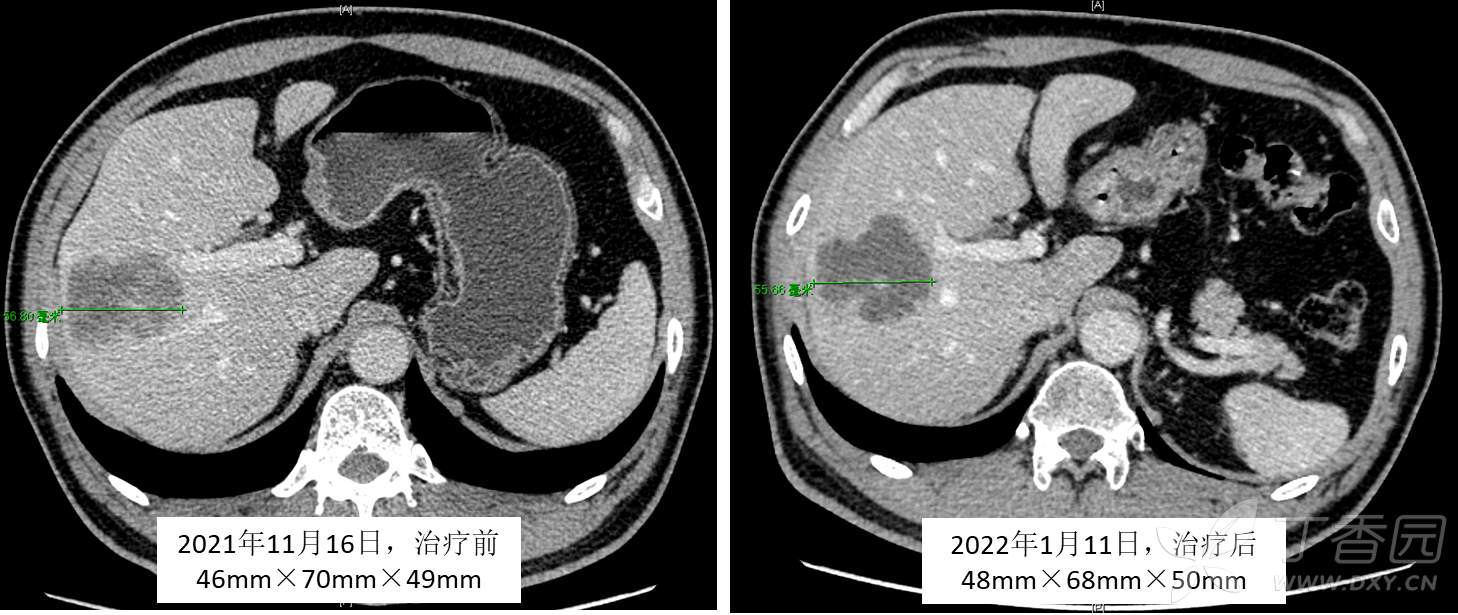

肝内胆管细胞癌预后差,大家应该都有感觉,何况这个病灶比较大,影像报告明确说多个卫星灶,面对“强敌”要联合作战!肝胆外科、肝胆肿瘤、肝胆介入、放疗、肝移植等等一起讨论制定了新辅助治疗策略:第一步先行免疫治疗+靶向治疗+放射治疗(范围右半肝,既灭活右半肝肿瘤及可能的周围转移灶,又促进将来的左半肝代偿),第二步行外科手术,第三步辅以靶向+免疫治疗。新辅助治疗6周后,CA199下降明显,从3410降到了2311;但是影像学评估变化不明显,如下图: